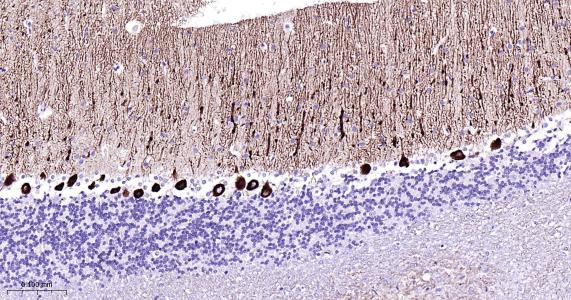

Paraformaldehyde-fixed, paraffin embedded Rat Cerebellum; Antigen retrieval by boiling in sodium citrate buffer (pH6.0) for 15 min; Antibody incubation with IP3 receptor Monoclonal Antibody, Unconjugated(bsm-61555R) at 1:200 overnight at 4°C, followed by conjugation to the bs-0295G-HRP and DAB (C-0010) staining.